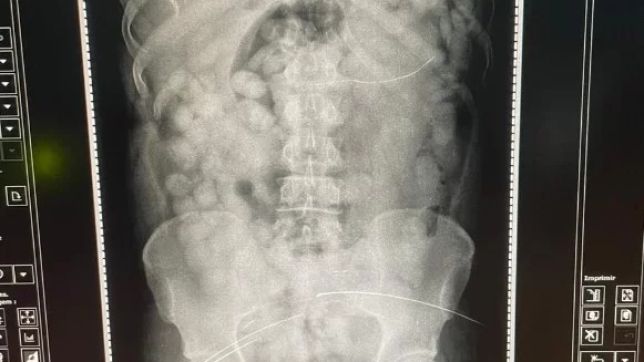

“O raio-x confirmou que havia cerca de 80 cápsulas no estômago, quantidade incomum, o que assustou a equipe policial. Em seguida, o preso foi encaminhado ao PSM, onde começou a expelir a droga ainda nesta manhã de sexta (8), sob custódia de policiais federais”, informou a PF por meio de nota.

A quantidade apreendida em casos assim costuma ser em torno de 40. O preso em Belém, porém, tinha o dobro. O tipo de droga, nessa modalidade, geralmente é cocaína salinizada, mais concentrada, acrescentou a PF.